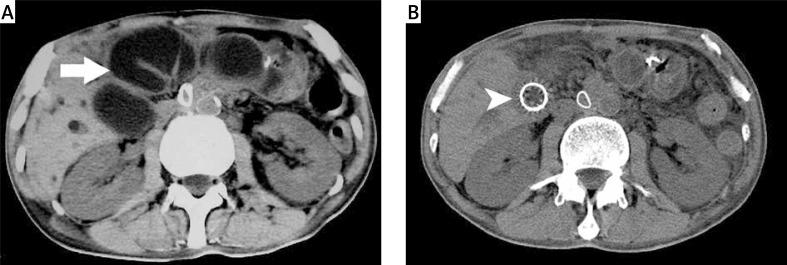

We analyzed 3 patients with malignant ALS after PD. They were treated by endoscopic enteral metal stent placement in our hospital. Meanwhile we retrospectively reviewed 49 cases with ALS after PD through available English literature. All these patients' clinical features, laboratory study, treatment and outcome were evaluated.

A total of 52 cases were analyzed in the study. The most common presenting symptoms of ALS after PD were jaundice (56.5%), upper abdominal pain (45.7%), fever (26.1%), and vomiting (23.9%). Sixty percent of ALS cases were caused by tumor recurrence. The mean time from prior surgery to diagnosis of ALS was 13.3 months. The rates of treatment with the endoscopic approach, percutaneous stenting or drainage, surgery, and the conservative method were 40.4%, 32.7%, 11.5%, and 15.4%, respectively. Endoscopic enteral metal stent placement proved more effective and less invasive in the treatment of malignant ALS after PD.

我们分析了3例PD术后发生恶性ALS的患者。在我院,他们接受了内镜下肠道金属支架置入术治疗。同时,我们通过现有英文文献对49例PD术后ALS患者进行了回顾性分析。对所有这些患者的临床特征、实验室检查、治疗及预后进行了评估。

本研究共分析了52例患者。PD术后ALS最常见的症状为黄疸(56.5%)、上腹部疼痛(45.7%)、发热(26.1%)及呕吐(23.9%)。60%的ALS病例由肿瘤复发引起。从上次手术至诊断为ALS的平均时间为13.3个月。内镜治疗、经皮支架置入或引流、手术及保守治疗的比例分别为40.4%、32.7%、11.5%和15.4%。内镜下肠道金属支架置入术在治疗PD术后恶性ALS方面被证明更有效且侵入性更小。